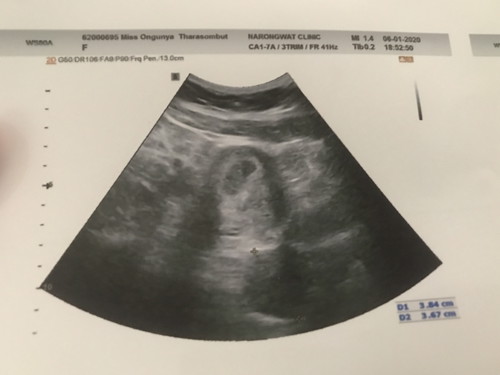

อันนี้อัลตร้าซาวตอน7w1d อยากรู้ว่าแม่ๆที่ได้แฝด เจอถึงแบบนี้รึป่าวคะ D1 D2 คือขนาดอะไรคะ พอจะมีแนวได้ลูกแฝดไหม ตื่นเต้นคะ

ถ้าแฝดต้องมีถุงตั้งครรภ์2ถุงค่ะ เเต่ภาพไม่ชัดเลย

ถุงไข่แดงก็คือถุงอาหารของตัวอ่อนในครรภ์คุณแม่ค่ะ จะมีให้1-3เดือนแรกหรือไตรมาสแรกนั่นเองค่ะ 😊

ความยาวปากมดลูกหรือป่าว

หมอบอกว่าอาจเป็นถุงอาหารหรือถุงไข่แดง แปลว่าอะไรค๊า ท้องแรกไม่รู้เรื่องจ้า

แบบนี้จ้า หมอบอกอาจเป็นถุงอาหารหรือถุงไข่แดง อีกถุง หมายความว่าอย่างไรคะ แม่